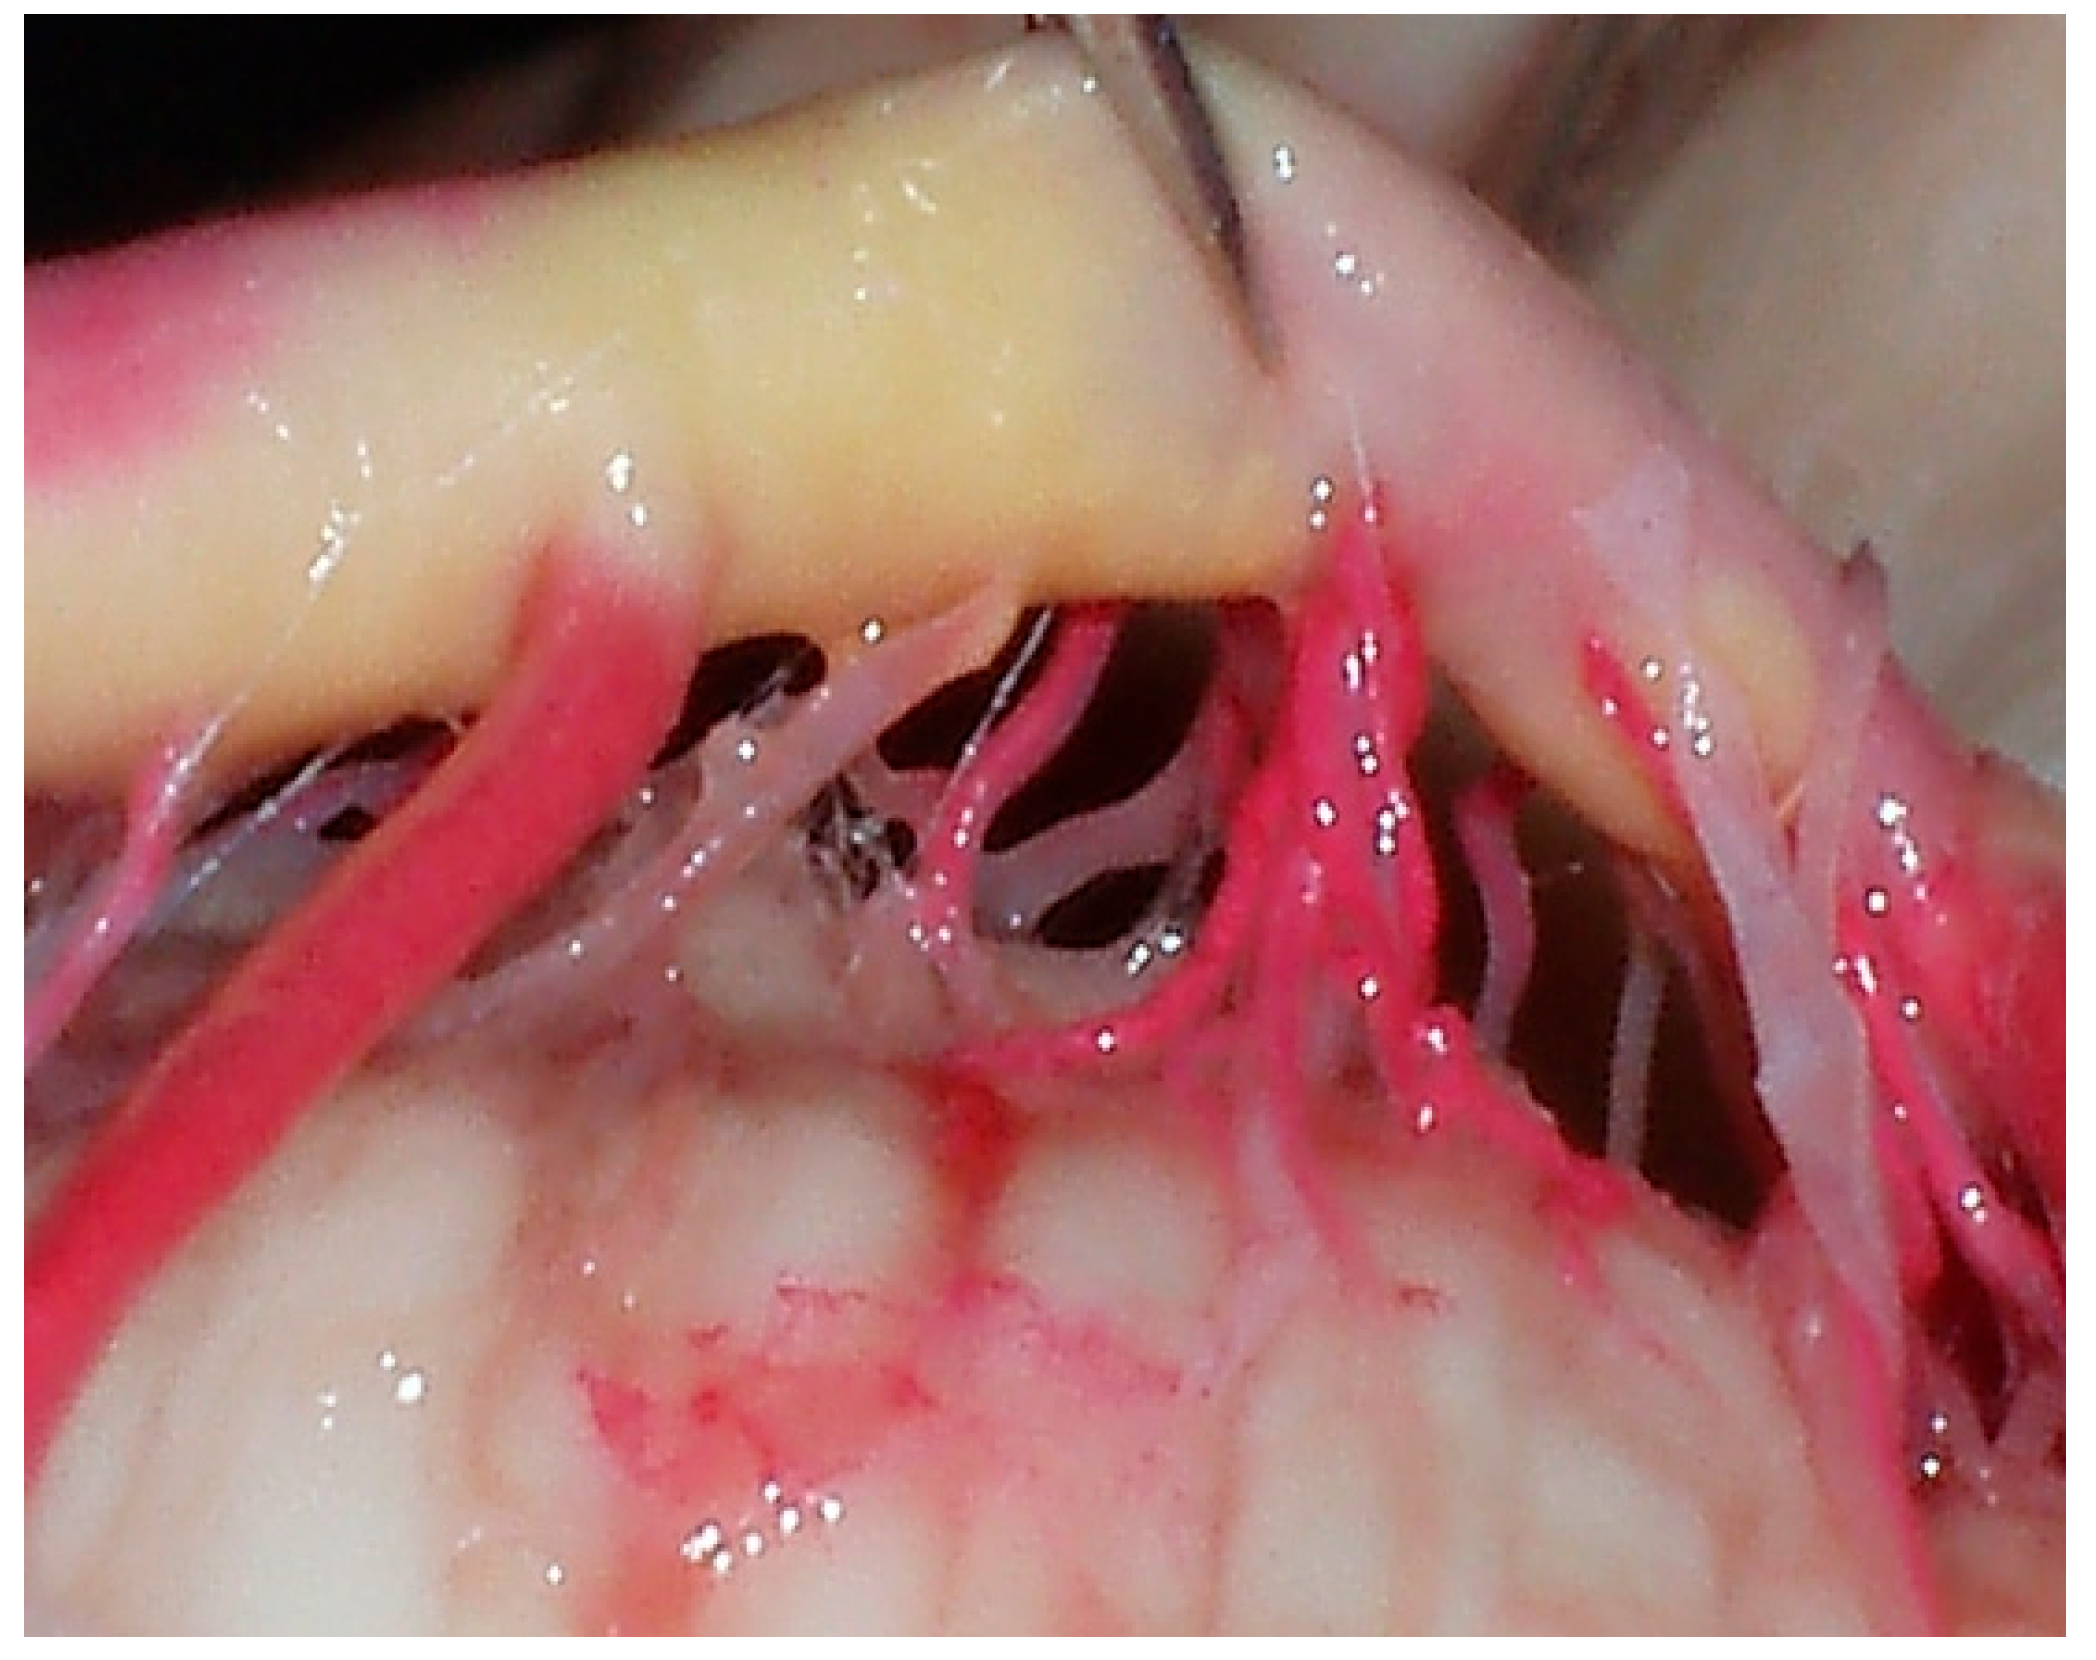

The brains were initially subjected to a thorough cleansing process, involving continuous irrigation with a 0.9% physiological solution. This step ensured the removal of any debris or clots that might interfere with the subsequent processes. Post-irrigation, the vertebral arteries of each brain were carefully perfused with a brightly colored red liquid latex. This latex perfusion was critical for delineating the intricate vascular structures during dissection. The perfusion process involved the precise placement of vascular clips at the posterior communicating segment and the PCA at the P2 level, ensuring targeted and efficient latex distribution. Following perfusion, the specimens were then submerged and fixed in a 5% formalin solution for a duration of 15 days. This fixation period was crucial for preserving the anatomical integrity of the brains for detailed microsurgical dissection (Figure 2).

Figure 2. Injection and washing technique. (A) Arterial system during its irrigation with physiological solution. (B) Perfused arterial system with colored latex.